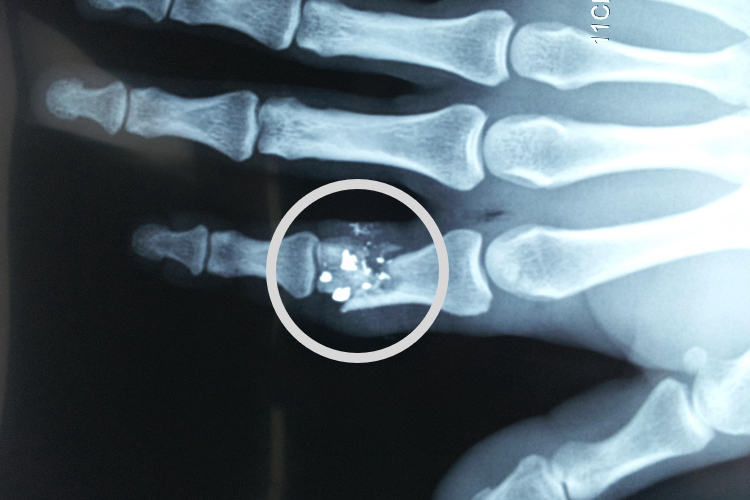

骨折患者在进行影像学检查时,可见局部出现清晰可见的裂纹,有时碎裂、缺损。病情轻重不定,但常伴有剧烈疼痛,患者正常工作、生活可受影响。